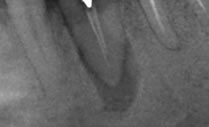

2009年7月

根菅充填より1年経過:来院時にあった根尖の透過像が消失しています。咬合痛もなくなったとのことです。